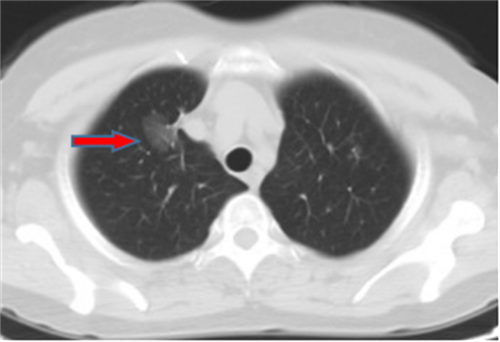

王女士,57岁,体检发现右下肺结节2月,术后病理诊断肺结节为肺隐球菌病。